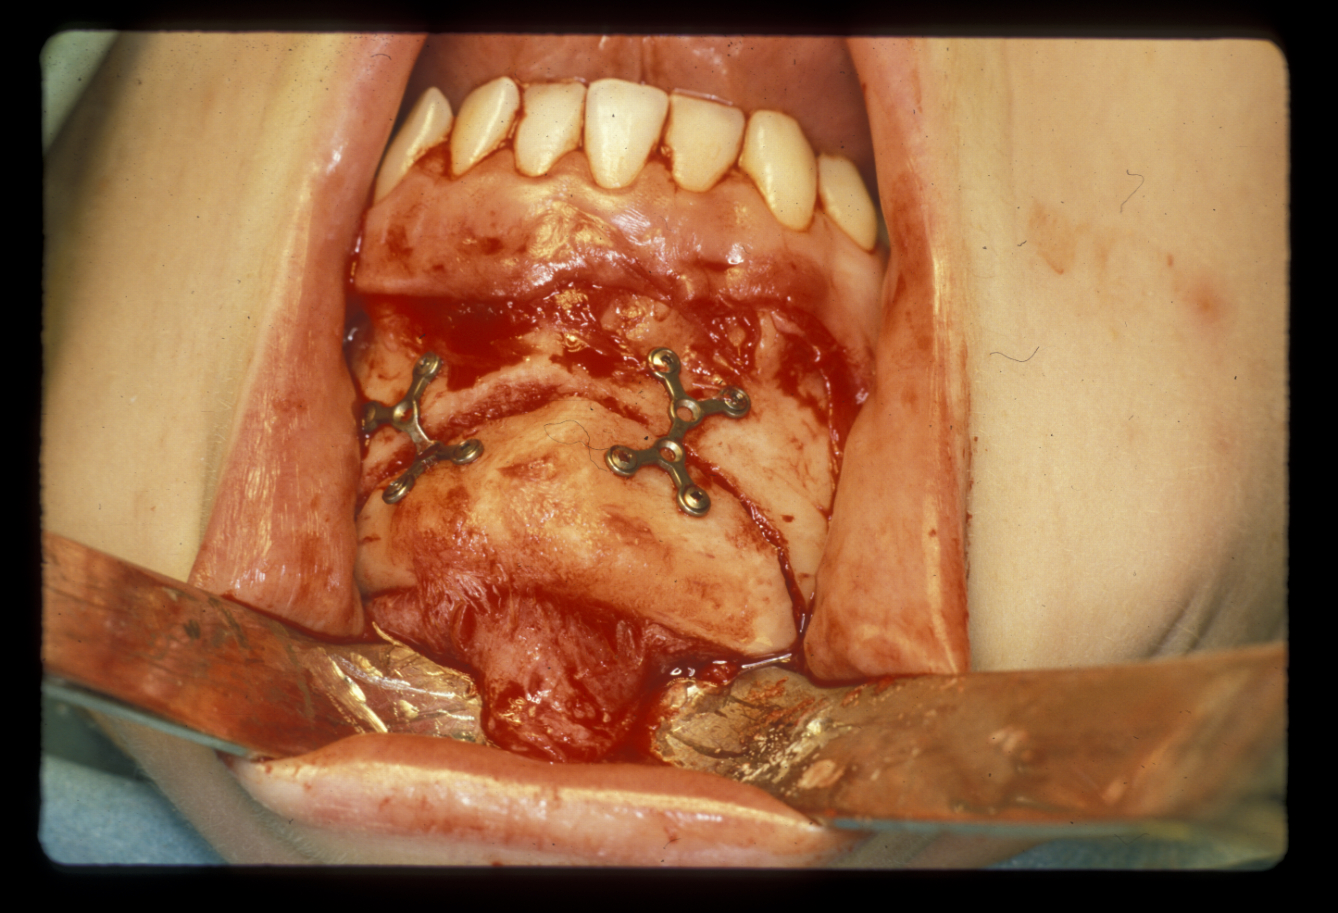

Genioplasty procedures use very similar principles to those of orthognathic procedures (Figure 10).

The chin is approached from an intraoral incision that exposes and protects the mental nerves. Bone cuts are made horizontally to retain the lingual muscle attachments. The chin is reduced by excising a middle portion of bone and inset to preserve the aesthetics of the cortical chin shape. It can be advanced by sliding forward. It is internally fixed using miniplates (Figure 11). Small asymmetries can be corrected in this way.

Augmentation genioplasty uses implants, either made from synthetic materials or a bone graft taken from the hip. The implant can be inserted by a skin incision under the chin (which is invisible from a front view) which is preferable for inert non-biological implants which have a lower inherent resistance to infection. Iliac crest grafts or sliding advancement genioplasties are far more common and a number of specific intra-oral miniplates have been devised to aid this surgery which also has a role in managing obstructive sleep apneoa. Almost inevitably, the aesthetic results using somebody’s own bone are superior to those achieved by using synthetic materials.